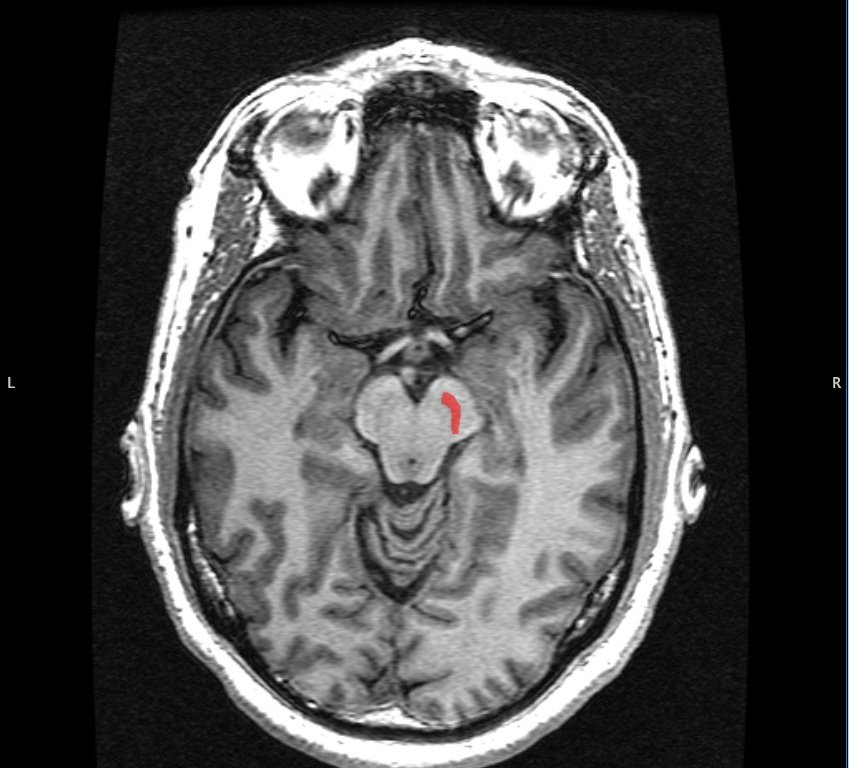

Figure 1: The substantia nigra (SN) nucleus in the midbrain.

Parkinson’s disease (PD) is an age-related, neurodegenerative movement disorder that causes a progressive loss of motor control. The disease is characterized by a loss of dopaminergic (DA) neurons in the substantia nigra (SN), a midbrain nucleus that modulates movement and reward functions. The SN is one of five subcortical nuclei that make up a network called the basal ganglia (BG). This network is in turn connected to other regions of the brain, including the cerebellum, thalamus, and primary motor cortex (M1), that together form the motor pathway responsible for our voluntary movements. The M1 is the output center of this pathway: it signals commands to muscles after its pyramidal neurons receive excitatory DA inputs from regions like the BG, and is regulated by surrounding inhibitory cells in the pathway known as parvalbumin-expressing (PV+) cells. Previous studies have shown reduced activation of M1 in PD patients, prompting questions about the impact of changes in M1’s input-output function.

[2] Image retrieved from: https://en.m.wikipedia.org/wiki/File:Substantia_Nigra.jpg